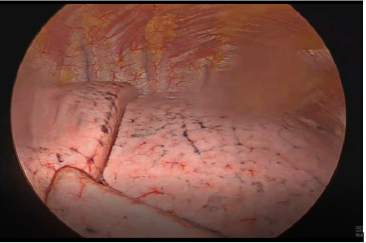

One week later, after maintaining pleural effusion even with a thoracic drain (drainage above 500mL day), she was submitted to Video-assisted thoracoscopic surgery (VATS) for pleural effusion drainage, pleural biopsy and pleurodesis (Figures 2 & 3). No suspicious implants were documented during VATS. The results showed no malignant cells and follow up thoracic x-rays revealed residual pleural effusion. She then underwent surgery with extemporaneous examination of the adnexal tumor. Histopathological findings were consistent with HGSOC and cytoreductive surgery was performed: left anexectomy, segmental resection of sigmoid and omentectomy. The pathology report documented a FIGO stage IIB with extrinsic infiltration of sigmoid onto muscularis propria. The tumor demonstrated solid and papillary patterns, and the classic slit-like spaces. The cells showed typical nuclear pleomorphism, prominent nucleoli, and numerous mitotic figures. Immunohistochemistry confirmed nuclear expression of WT1, strong diffuse p16 immunoreactivity and abnormal pattern of p53 expression (mutation-type labelling) represented by strong diffuse staining in > 80% of tumor cells. The histological and immunohistochemical findings were of a HGSOC (Figure 4). Ascitic citology was negative for malignant cells. Postoperative CA125 was 43.3U/mL, she had no clinical evidence of ascites or pleural effusion and started adjuvant chemotherapy with carboplatin/paclitaxel (Figure 5).

The patient’s initial presentation pointed to a diagnosis of an advanced stage IVA ovarian carcinoma with the presence of ascites, recurrent pleural effusion, adrenal tumor and markedly elevated CA125. Despite its rarity and the fact that it is a diagnosis of exclusion, classic MS and its variants should be remembered as it can also lead to an increase in CA 125. Taking this into account the evaluation of pleural fluid is essential for proper staging and treatment. In this case the consecutive analysis of pleural effusion negative for malignant cells raised the hypothesis of Classic MS, which specifically refers to ovarian fibroma, or of pseudo-MS related to other benign or malignant abdominal and pelvic tumors. For clarification of the condition and in the face of recurrent pleural effusion the patient was submitted to VATS. We highlight the importance of this procedure in cases like this, considering the advantages it presents, in particular: visual evaluation of the pleura, direct tissue sampling (including pleural biopsy), and therapeutic intervention (in this case pleurodesis). Thus, we were able to say with greater certainty that there was no neoplastic thoracic involvement. After exclusion of thoracic involvement, the patient underwent primary surgery, during which the extemporaneous examination of the adnexal tumor revealed the diagnosis of malignancy (HGSOC) and cytoreductive surgery was performed.